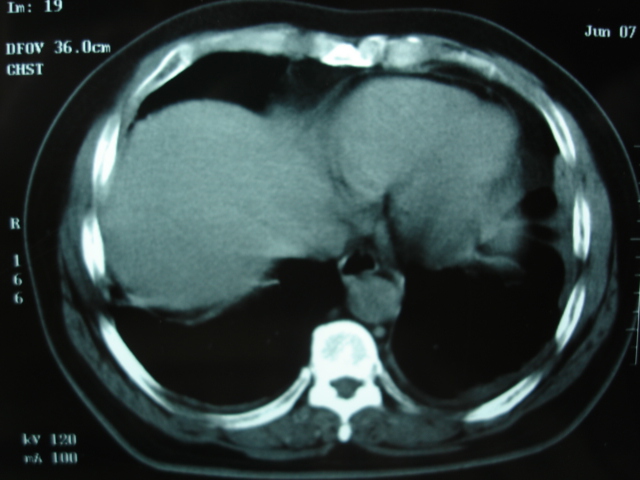

第一次ct2009.6.4

第二次ct2009.6.7 住院后ect未见异常,查痰(阴性)大量抗菌素抗炎一个月后病灶明显变小,7月5号出院后回家后口服抗菌素45天